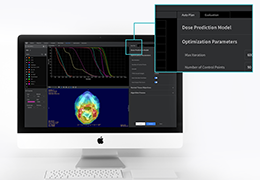

成像智能。

Eclipse 成像智能功能提供强大的处理能力和最佳质量的影像,同时减少质量错误并提高剂量效率。

凭借 AI、专有算法和先进的影像处理能力,提供出色的影像质量和无与伦比的诊断信心。

与标准影像处理相比,智能降噪功能可使客户降低辐射剂量,而不会损失影像质量。这在新生儿和儿科成像中尤其重要,在这种情况下以尽可能低的剂量成像至关重要。

提供相配视图选项,以减少所需的曝光次数,并提供更清晰的感兴趣区域视图。